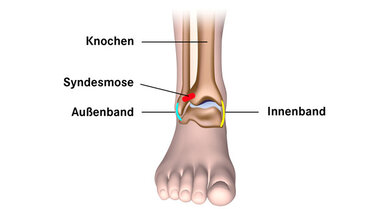

Am Sprunggelenk sind viele Bänder. Die Bänder halten die verschiedenen Knochen im Sprunggelenk zusammen. Und die Bänder machen das Gelenk stabil. Das Sprunggelenk ist von diesen Bändern umgeben:

- Außenband

- Innenband

- Syndesmose

Am Sprunggelenk sind viele Bänder. Das Bild zeigt das Außenband, das Innenband und die Syndesmose